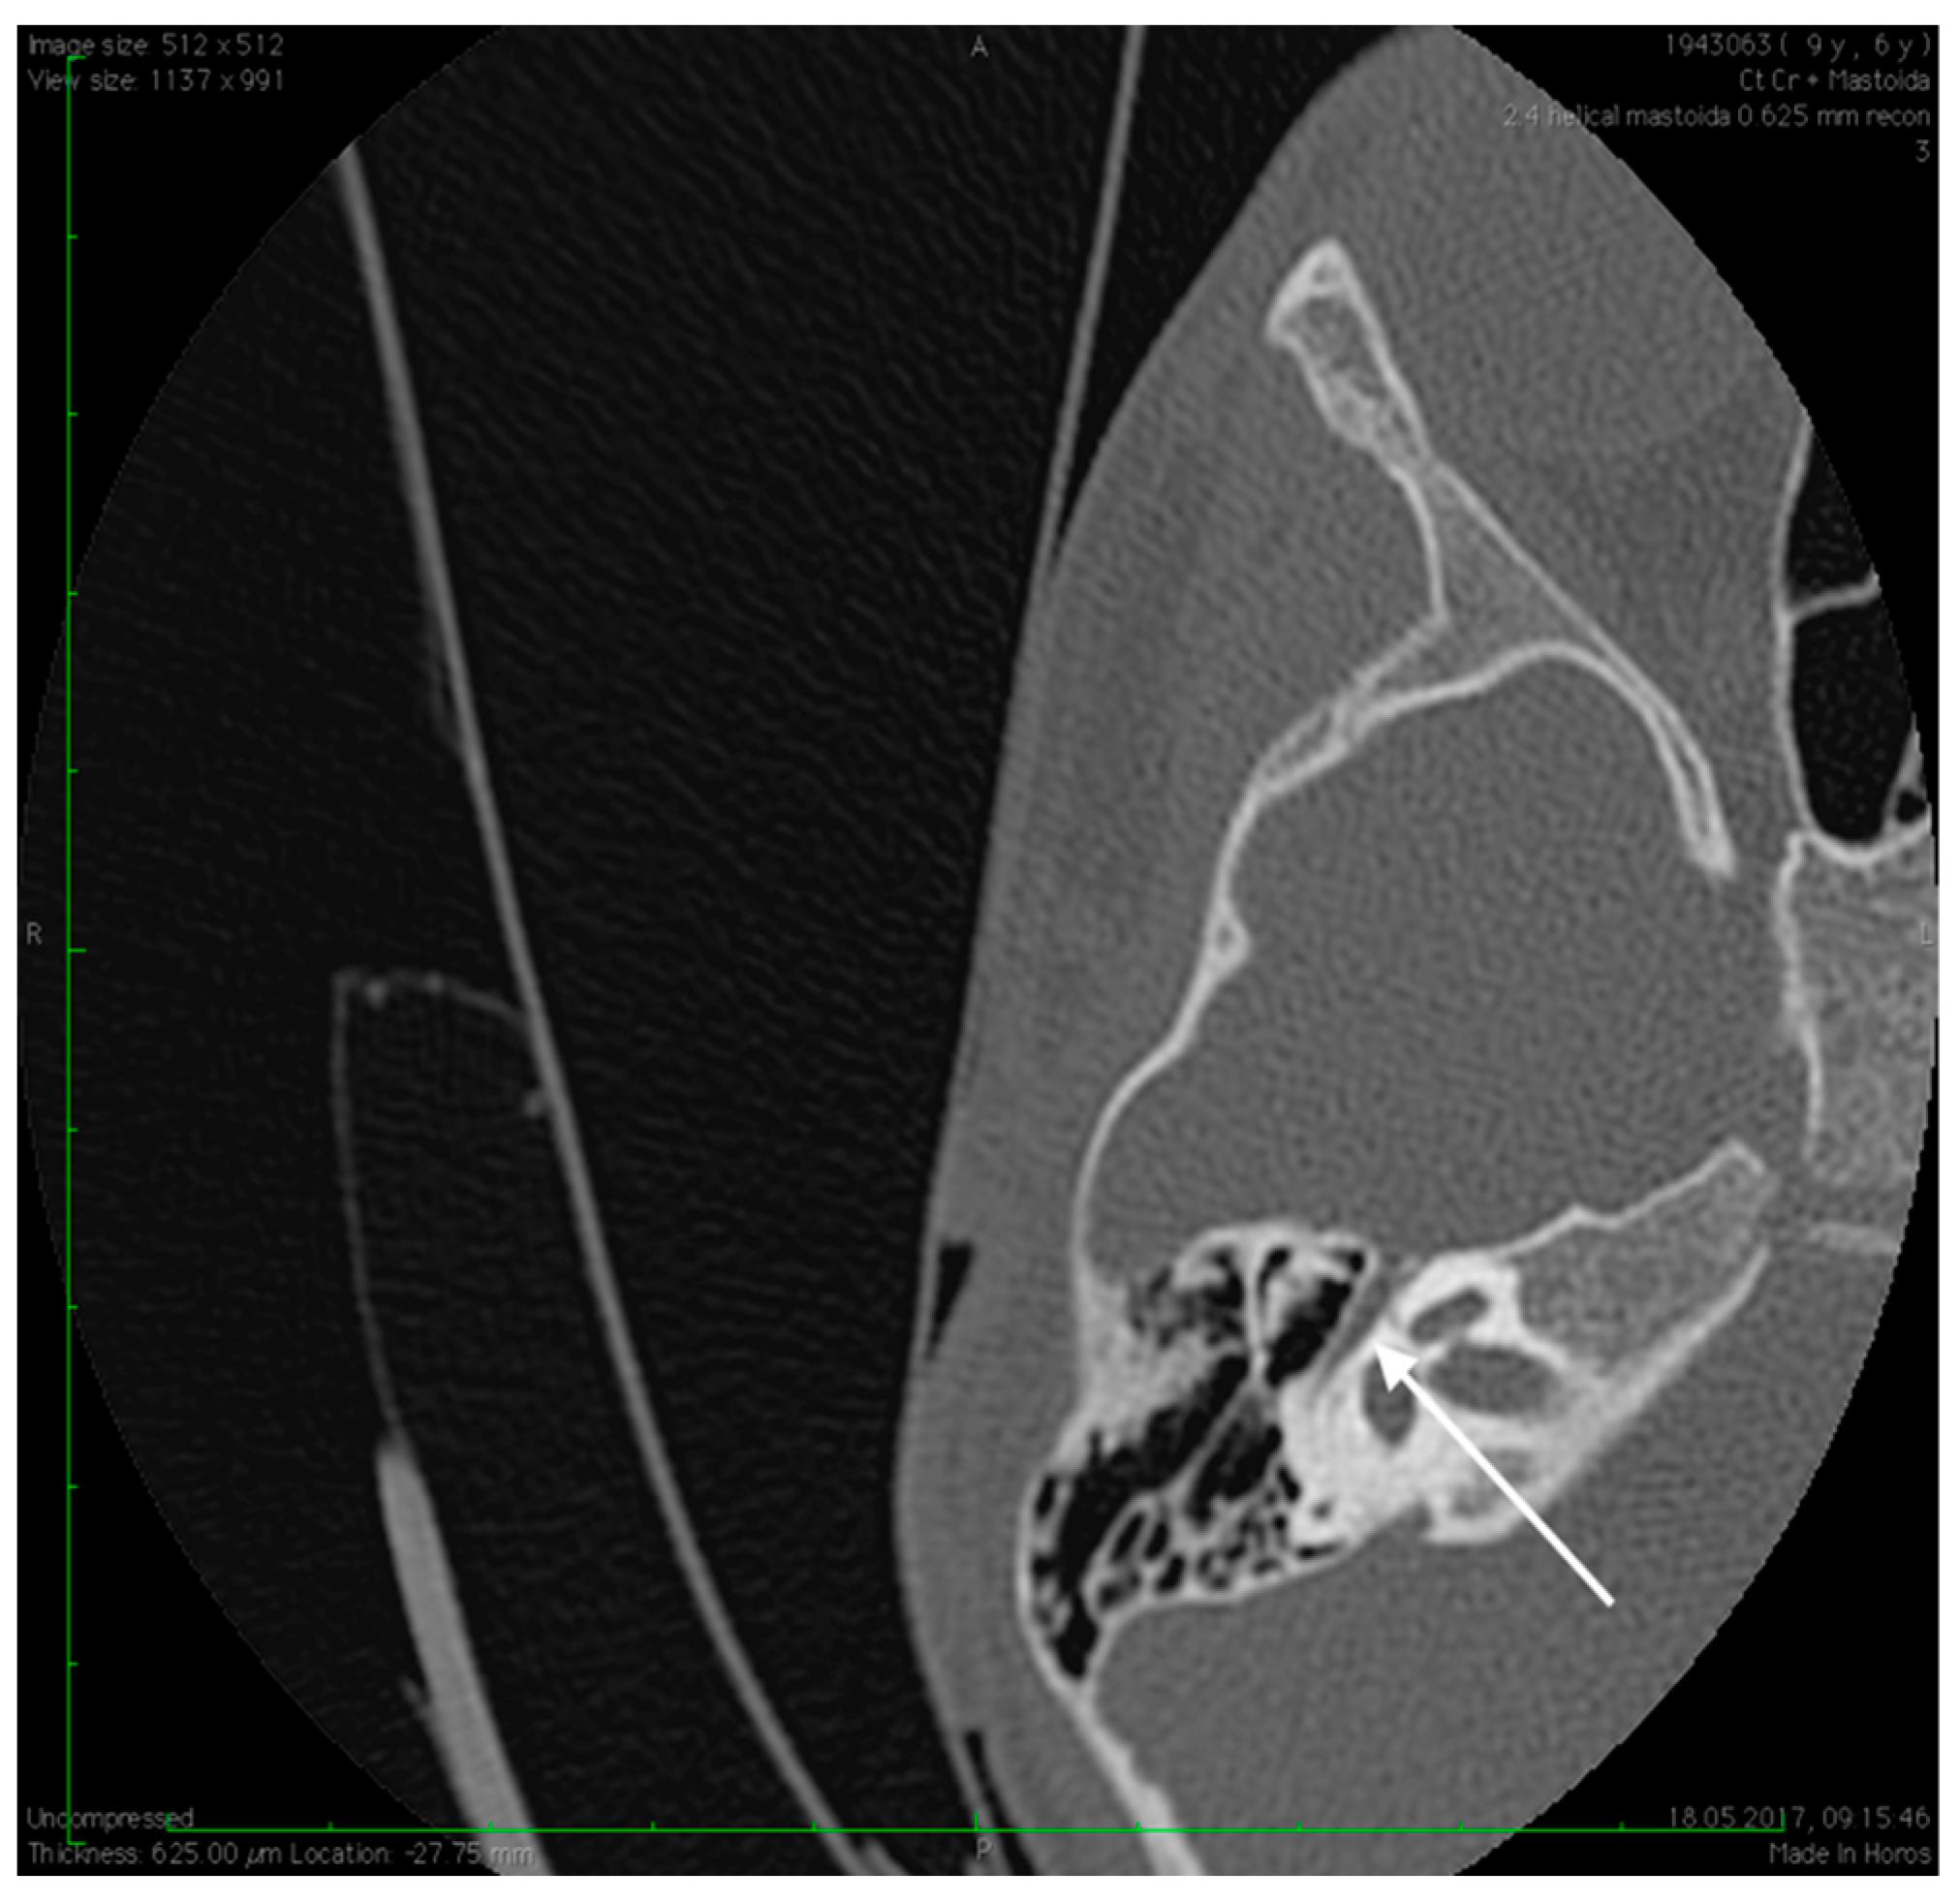

Figure 4.

High resolution axial CT scan of right temporal bone exposing the unusual wide facial canal and the missing oval window on the right side (arrow).

Figure 5.

High resolution axial CT scan of right temporal bone exposing the missing foramen spinosum (arrow).

Preoperative CT imaging of middle ear surgery patients is mandatory and careful interpretation of the results can sometimes prevent accidental injuries brought to a PSA. The usual findings are a small, abnormal, canaliculus leaving the carotid canal or the facial nerve, a straight line structure crossing over the promontory, an unusual widening of the fallopian canal or a different canal parallel to it between the geniculate and the oval window niche and absence of the foramen spinosum []. Our CT findings coincide with some of the aforementioned signs, as there can be seen no trace of the foramen spinosum in the affected ear (Figure 5), in contrast to the contralateral ear (Figure 3). There is also a widening of the facial nerve canal that can be observed in Figure 4. It came as no surprise that the stapes could not be described in the CT images, as the literature review acknowledges the possible stapes malformations that come along with PSA.